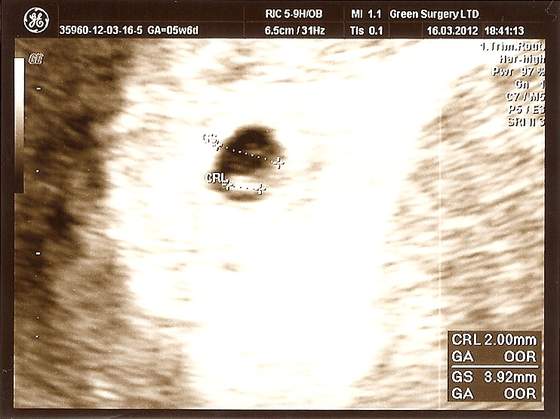

niesamowite...boisz się troche jak to będzie z podwójnym szczęściem? :-)A oto moje zdjecie USG- 5t6d. Pecherzyk -3,92mm a dzidzia 2mmCos mi ten pecherzyk jakis maly ale ona dziwnie go wyliczyla bo na szerokosc a nie dlugosc, zreszta nie wiem... Oby tak dalej